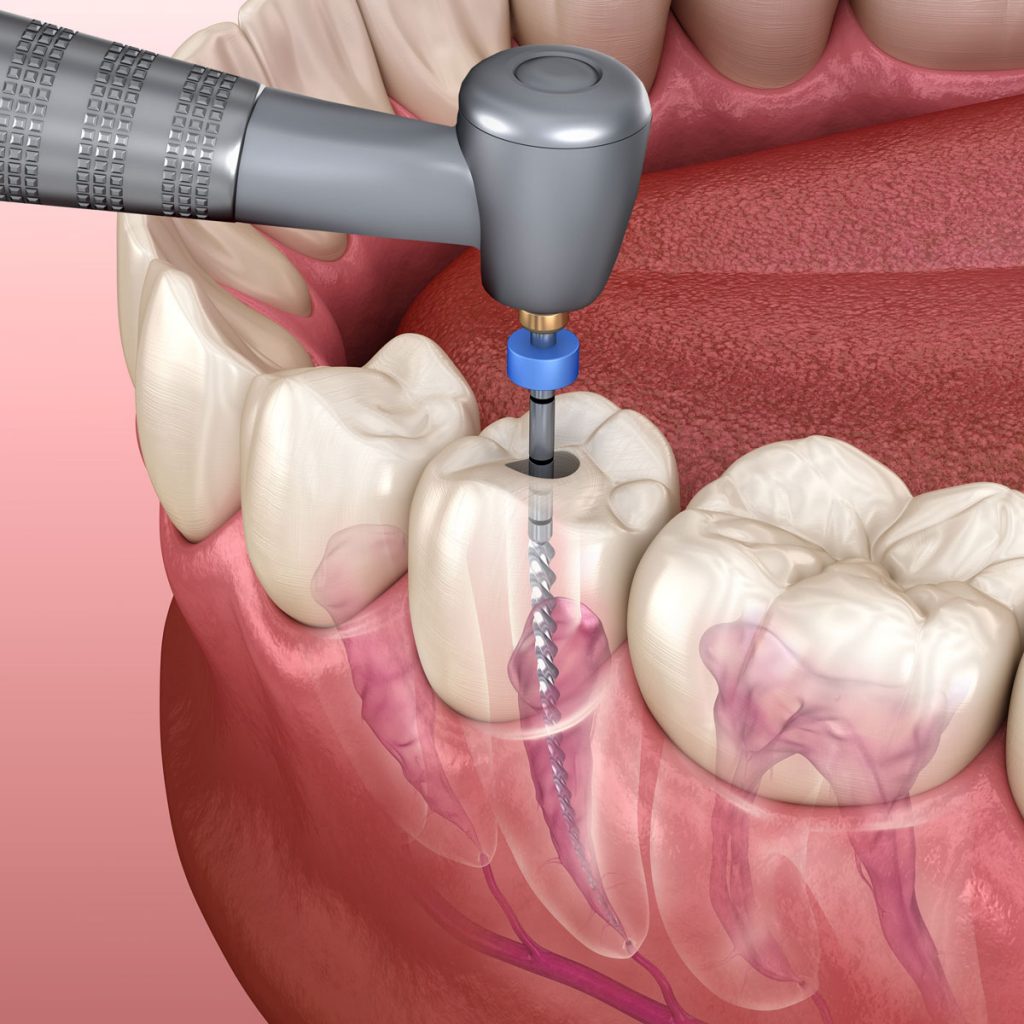

Cilj endodontskog tretmana je uklanjanje inficiranog ili oštećenog živca (pulpe), temeljno čišćenje i dezinfekcija kanala, te njihovo hermetičko zatvaranje kako bi se spriječila ponovna infekcija.

Dijagnostika

Anestezija

Uklanjanje pulpe

Mašinska obrada

Dezinfekcija

Punjenje kanala